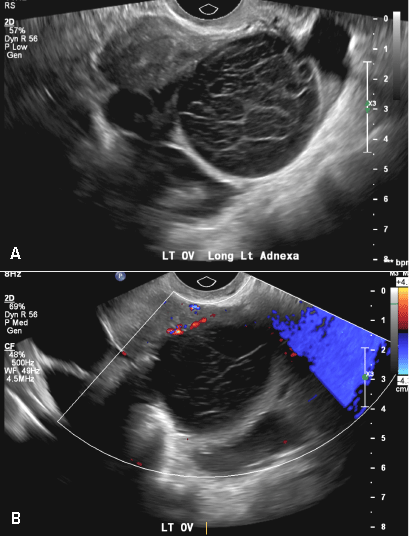

(C) Endometrioma INCORRECT

This mass is a well-circumscribed hypoechoic cyst with homogeneous ground glass or low level echoes and increased through transmission.1 It is also avascular without solid components.